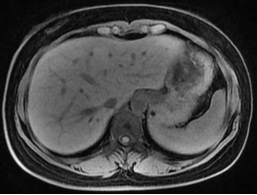

核磁检查,作为正常人肝脏,右为酒精性肝硬化(肝脏缩小,表面,凹凸不平,脾脏肿大)